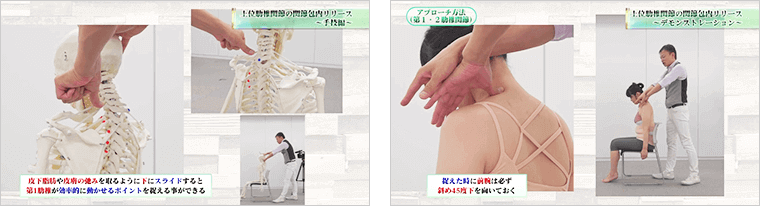

DISC1では、そんなAKS療法®の全貌やメカニズムを徹底解説します。

DISC2では、仙腸関節への関節包内リリースについて解説します。

日常動作さえままならない患者さんには、「肋椎関節への関節包内リリース」を施術することを推奨します。

DISC3では、患者さんに一切負担の無いソフトなタッチで、

肋椎関節を瞬時に調整するテクニックを伝授します。